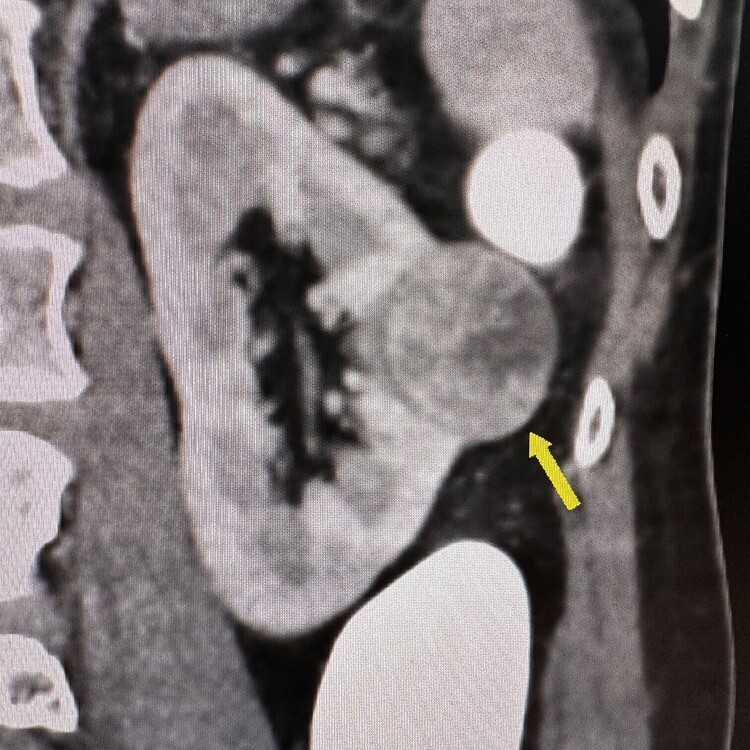

CT Colonography

Early kidney cancer found at CT colon in a 55 years old man. The man had no symptoms of this cancer which was promptly removed and cured.